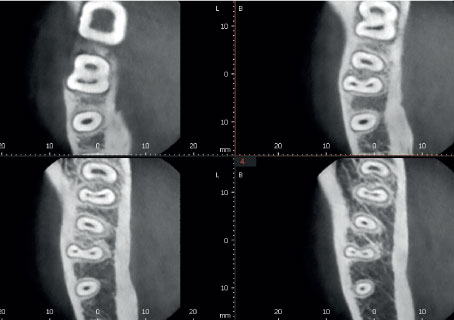

Режим Эндо с высочайшим разрешением

Режим Endo с объемом 4x4 см и размером вокселя 49,5 микрон оптимизирует обработку областей, представляющих повышенный интерес. Он идеально подходит для эндодонтии, поскольку стоматолог может получить изображение с высоким разрешением вокселей.